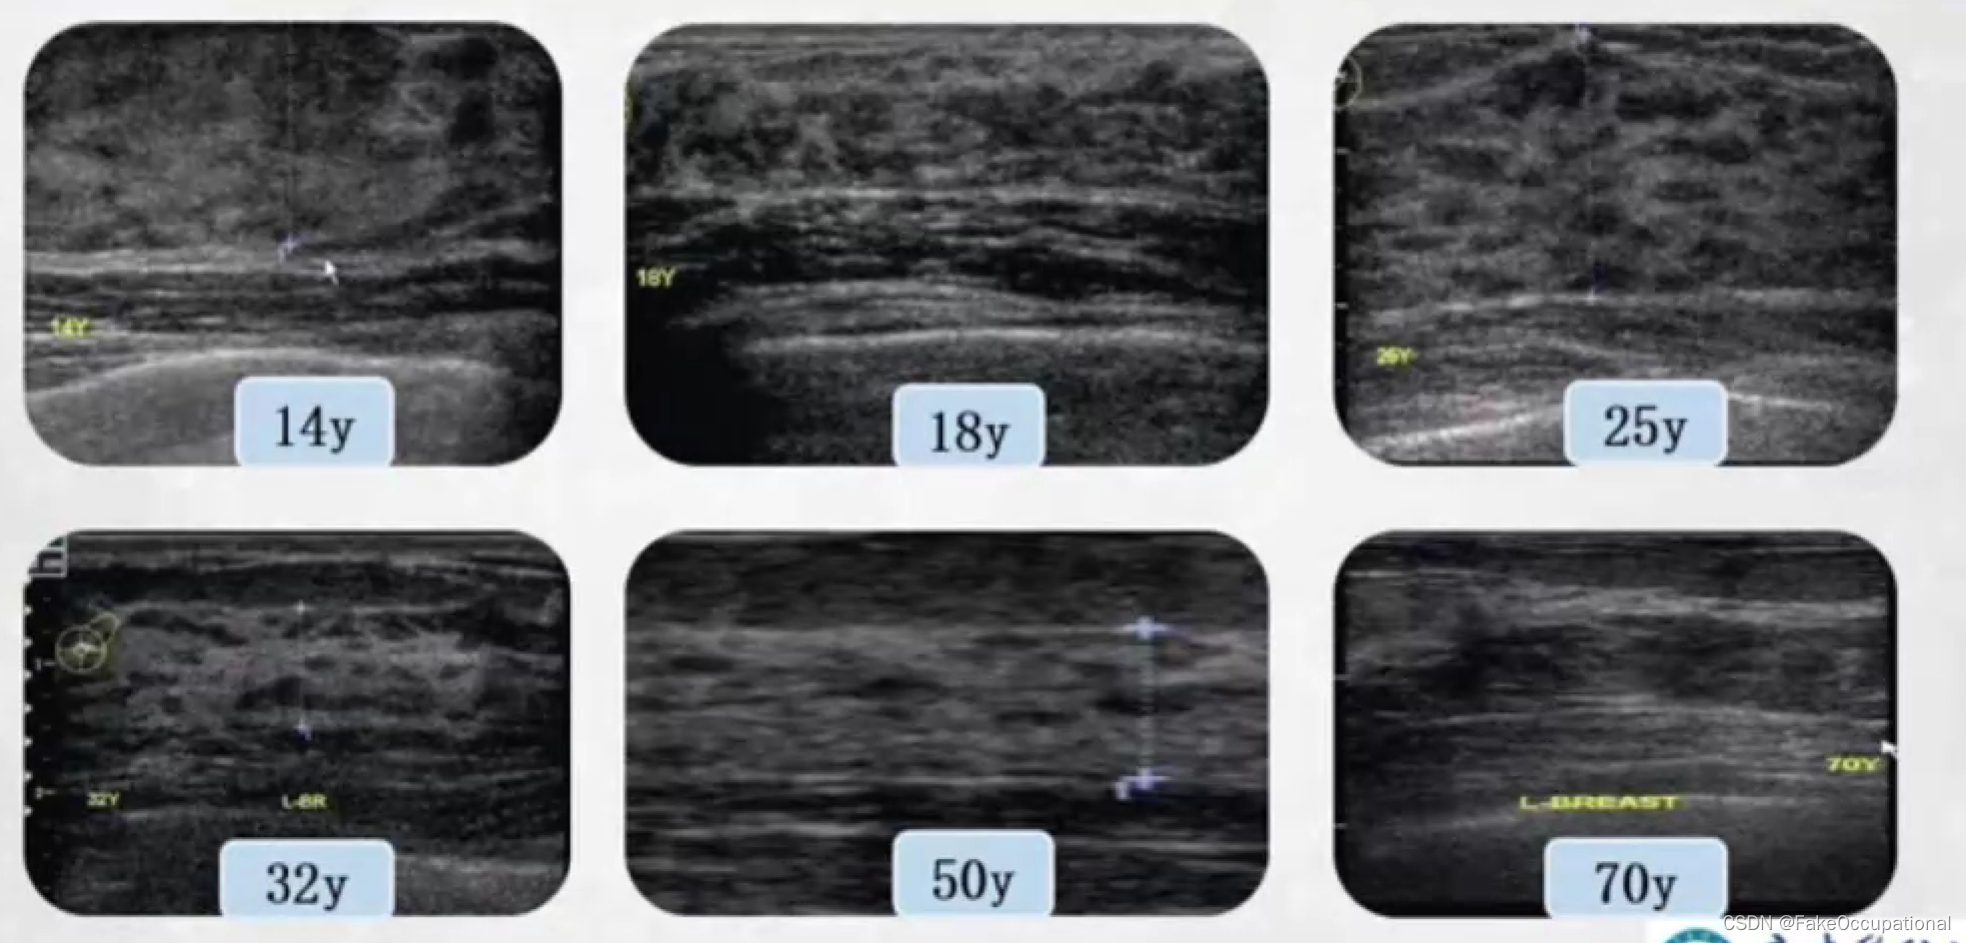

正常乳腺超声表现

- 高回声的皮肤层,低回声的皮下脂肪层